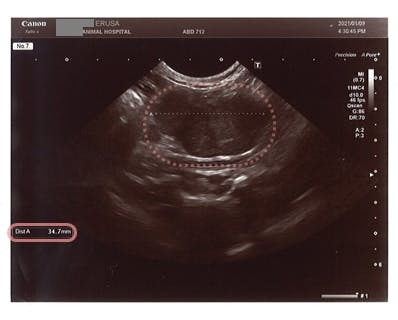

(資料❸:腹部エコー検査結果)

・ピンクの点線○の部分が肉芽腫です。

腹部に直径約3.5cmの肉芽腫が検出されています。

ウェット型特有の腹水や胸水は